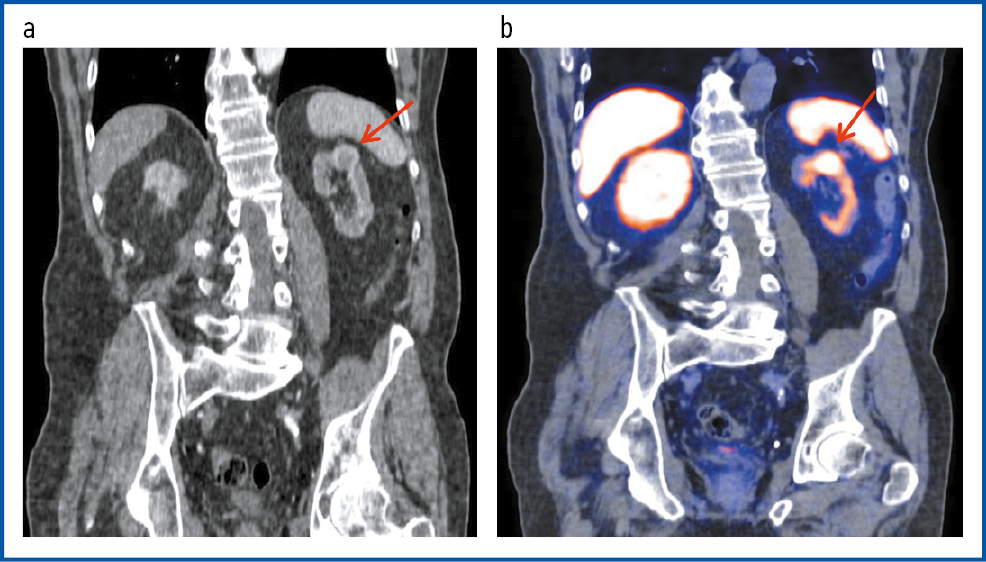

Рис. 3. Пациент С., 74 года. ПЭТ/КТ с 18F-PSMA. В коронарной проекции КТ (a) и ПЭТ/КТ-исследовании (b) левая почка уменьшена в размерах, с наличием в верхнем сегменте кистозно-солидного образования с гиперфиксацией РФП, SUVmax 12,8, размерами 26 × 23 мм.

Fig. 3. Patient S., 74 years old. PET/CT with 18F-PSMA. In the coronary view of CT and PET/CT imaging, the left kidney was reduced in size, with the presence of a cystic-solid mass in the upper segment with RPA hyper fixation, SUVmax 12.8, 26 × 23 mm.